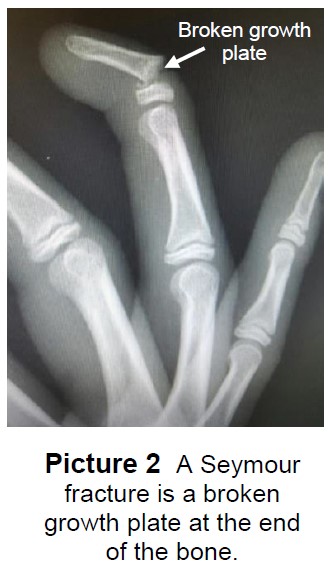

- Crush injuries to the fingertip can cause 2 types of bone fractures:

- Seymour Fracture - a break in the growth plate (Picture 2).

- Tuft fracture - a break in the bone closest to the tip of the finger.

- Both types of fingertip fractures are treated with a splint or cast.

- These keep the bone from moving so it will heal.

- Your child may wear the splint or cast for 2 to 4 weeks.